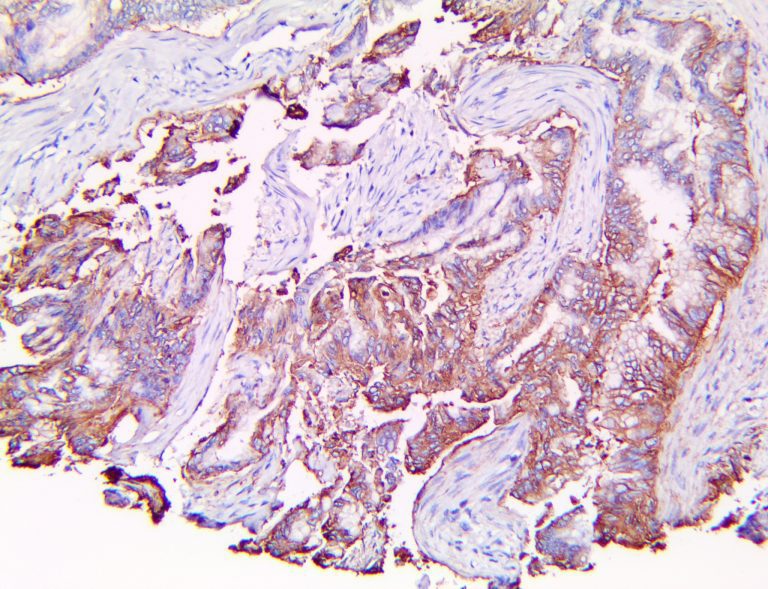

The first cytokines released are interleukin 1β (IL-1β) and tumor necrosis factor-α (TNF-α), which attract a variety of circulating white blood cells (WBCs) to the infection site, including neutrophils, monocytes, macrophages, and natural killer (NK) cells. This response, along with the antipathogenic chemicals released by these cells (i.e., complement), comprise the innate immune response. These cells directly attack the invading pathogen and also release additional cytokines, chief among them interleukin-1 and 6 (IL-6). IL-6 is essential for invoking the adaptive immune response, which calls T-cells, B-cells, and T helper (Th) cells to the infection site. IL-6 also stimulates further recruitment, proliferation and activation of macrophages.

This activation induces inflammatory monocytes to highly express IL-6, starting a localized and then systemic cascade effect that results in hyperproduction of IL-6, which accelerates the inflammatory process. Because IL-6 also increases vascular permeability, excessive levels cause blood vessels to become very leaky. This, along with clotting factors released from vascular endothelial cells, stimulates the coagulation cascade, resulting in microthrombosis (tiny clots), which leads to ischemia and tissue death of the kidney, intestines, heart, liver, brain and extremities.